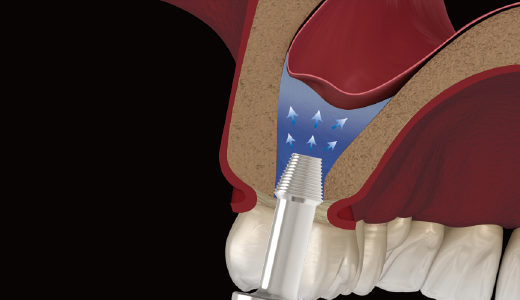

상악동 거상술 시 : 대량의 골이식재를 Window 입구까지 정확히 전달

측방접근법

1. Window 형성 후 거상

2. Bone Carrier로 골이식재 주입